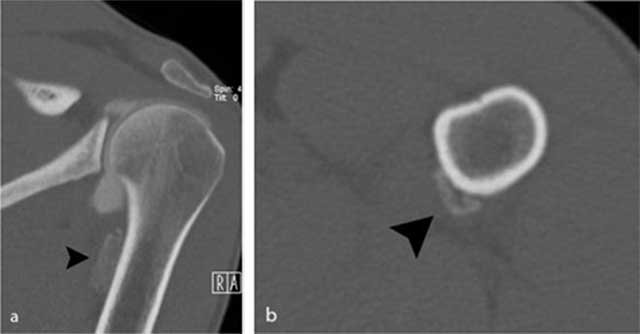

Figure 3

Additional CT images of the proximal humerus. a) Oblique coronal reformatted images and b) axial reformatted images reveal the presence of an extra-articular calcification (black arrowhead) near the insertion of the teres major tendon.

Standard radiography in the acute phase may reveal a small subtle fleck of bone at the periosteal insertion of the teres major. This should not be misinterpreted as a bony Bankart lesion, as the lesion is located slightly more inferiorly. CT may be useful to diagnose a subtle avulsion and for follow-up showing progressive peripheral calcification and ossification and ultimately fusion with the underlying cortex [4]. Although MR (arthrography) is currently a routine imaging tool for evaluation of shoulder trauma in sports trauma, it is important to analyze the images beyond the margin of the joint and scrutinize for extra-articular lesions [8]. Therefore, at least one imaging sequence with a large field of view should be used.